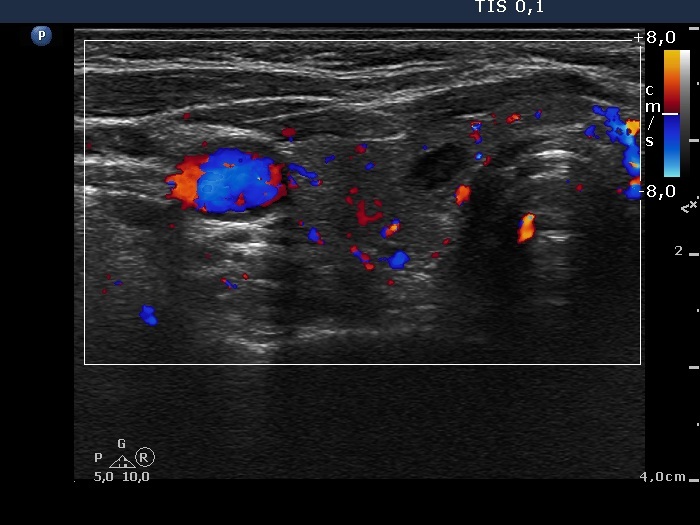

Ultrasonography. The thyroid was moderately hypoechogenic. There were several discrete lesions in the right lobe without any oncological significance. There was a hyperechoic nodule in the lower third of the left lobe, which corresponded to the positive focus on PET CT scan.